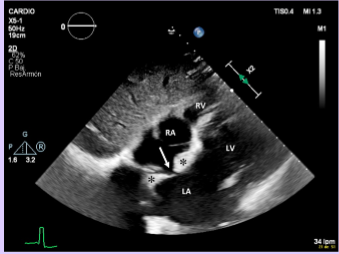

Right heart thrombus

Relatively common.

Associated with pulmonary embolism.

Better seen on TEE than TTE, due to increased visualization of the SVC and IVC.

59